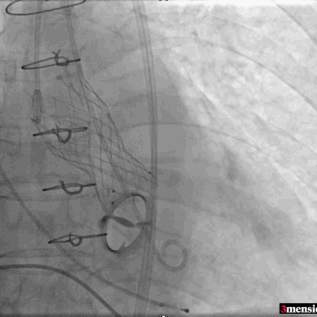

植入后瓣架深度

术中导丝跨瓣后20mm球囊预扩,超声判断冠脉风险尚可,植入L23 VenusA Plus可回收瓣膜位置良好,用23mm球囊后扩支架下缘,微少量瓣周漏。

术后即刻血压135/65mmHg,狭窄解除,释放后超声测量瓣下支架长度6mm标准位释放瓣膜位置完美。整台手术用时不足1.5小时,麻醉、超声等团队全程协作为手术顺利完成保驾护航。